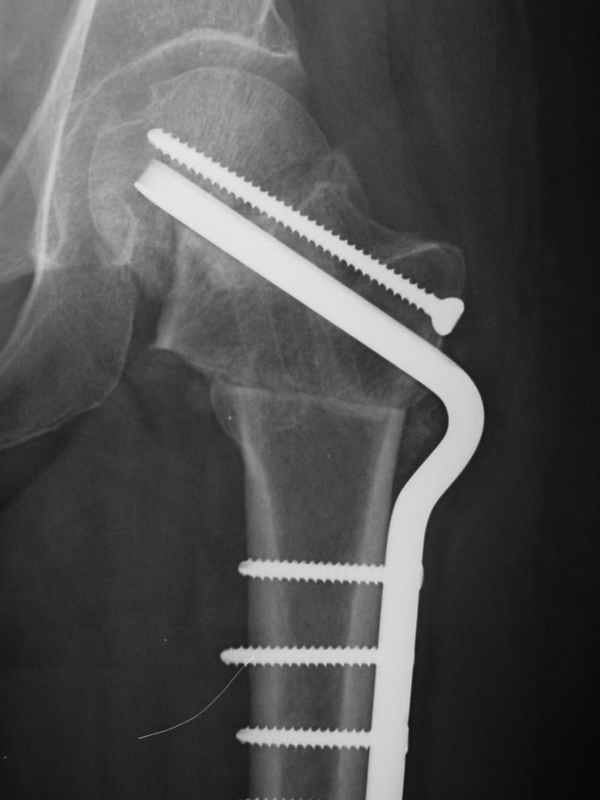

Нелеченный перелом шейки бедра / Neglected femoral neck #

Глубокоуважаемые коллеги,Вчера обратился мужчина 31 г. Травма 2 месяца назад, лечился в одном из городов области. Был не самый тяжелый перелом таза, который проведен консервативно. С ним и связывали невозможность поднять ногу.

Однако на сегодняшнем снимке обнаружился перелом шейки бедра. Больной уже ходитс частичной нагрузкой. Учитывая срок и картину на снимке, что предпринять? У нас предложены варианты 1)не оперировать, 2)закрыто 2 спонгиозных винта, 3)вальгизирующая остеотомия. Эндопротез как-то даже в список включать пока не хочется. Какие есть соображения? Что из перечисленного или что-то другое выбрать и почему? Заранее спасибо.

Dear colleagues,A male 31 years old treated elsewhere after not severe pelvic fracture, was managed non operatively. So the injury looked as a reason of his inability to elevate the leg. However at the recent x-rays the neck fractire was found. The patient already has been walking with partial weight-bearing.Looking at the x-rays and the time since the injury, what is the optimal treatment for now? We discussed 1)leave as is, 2)2 cancellows screws as is, 3)valgus osteotomy. Total hip replacement looks unnecessary yet.What is your opinion? Which option from the listed or something else should be preferred and why?THX in advance.

При явно выраженном варусе и флексионных состояниях после сросшихся переломов шейки бедра у молодых рекомендуется реконструктивная операция по исправлению варуса для предотвращения раннего деформирующего артроза, приводящего в результате переднего импинжмента, как показано на снимке.

Межвертельная вальгусная остеотомия представляет наименьший риск среди всех реконструктивных операции в проксимальной части бедра, создавая наилучшие биомеханические условия (увеличивается сила абдукторов, увеличивается сила суставной реакции, уменьшение рычага моментов абдукторов и уменьшение скольжения) и при меньшем риске повреждения кровоснабжения головки, где обычно в 90% случаях достигается отличный результат при применении метода для лечения ложных суставов шейки бедра.

По моему, 120 градусная угловая пластина blade plate решит все проблемы, только необходим предварительный расчет угла остеотомии, и во время фиксации пластины не забыть латерализацию бедра, иначе ось конечности от варуса перейдёт в нежелательный вальгус.

the best option is valgus osteotomy with DHS and also additional canceelous screw fixation. the idea is to convert vertical shear foeces to horriszontal